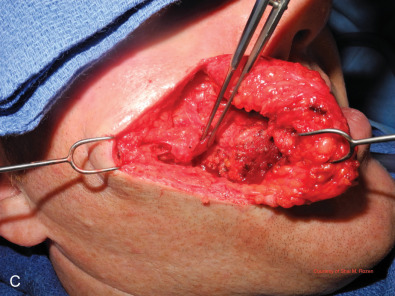

Muscle Injury

Although not a common cause of facial paralysis, muscle injury may have similar effects and clinical presentation as nerve injuries, especially in the setting of acute trauma, in which both muscle and nerve may be contused. Over time, when the nerve recovers the muscle injury usually becomes more apparent since motion is seen in the proximal innervated muscle but animation is inhibited because the distal muscle is detached and will not produce the intended motion at the muscle insertion. These injuries usually result in more focal akinesia compared with proximal nerve injuries ( Fig. 1.5.4 ).